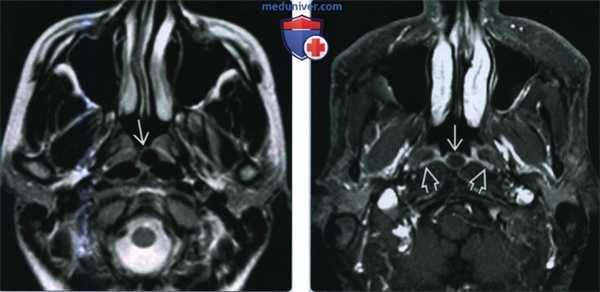

(Слева) При МРТ Т2ВИ в акси-альной проекции по средней линии носоглотки визуализируется киста Торнвальда В, вследствие высокого содержания белка интенсивность сигнала низкая. При более высоком содержании воды интенсивность сигнала обычно выше. Обратите внимание на то, что киста отделена от глубоких мышц, что говорит о ее поверхностном расположении в пределах слизистой оболочки.

(Справа) При Т1 ВИ FS с КУ в аксиальной проекции определяется характерная киста Торнвальда, которая имеет небольшие размеры и не накапливает контрастное вещество. Слизистая оболочка накапливает контраст и выглядит как тонкая белая линия.